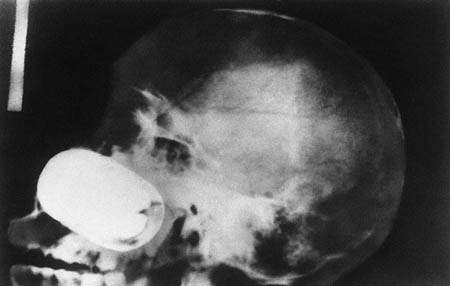

有顆手榴彈在囚犯的顱骨內

圖片來自:http://www.po-kaki-to.com/